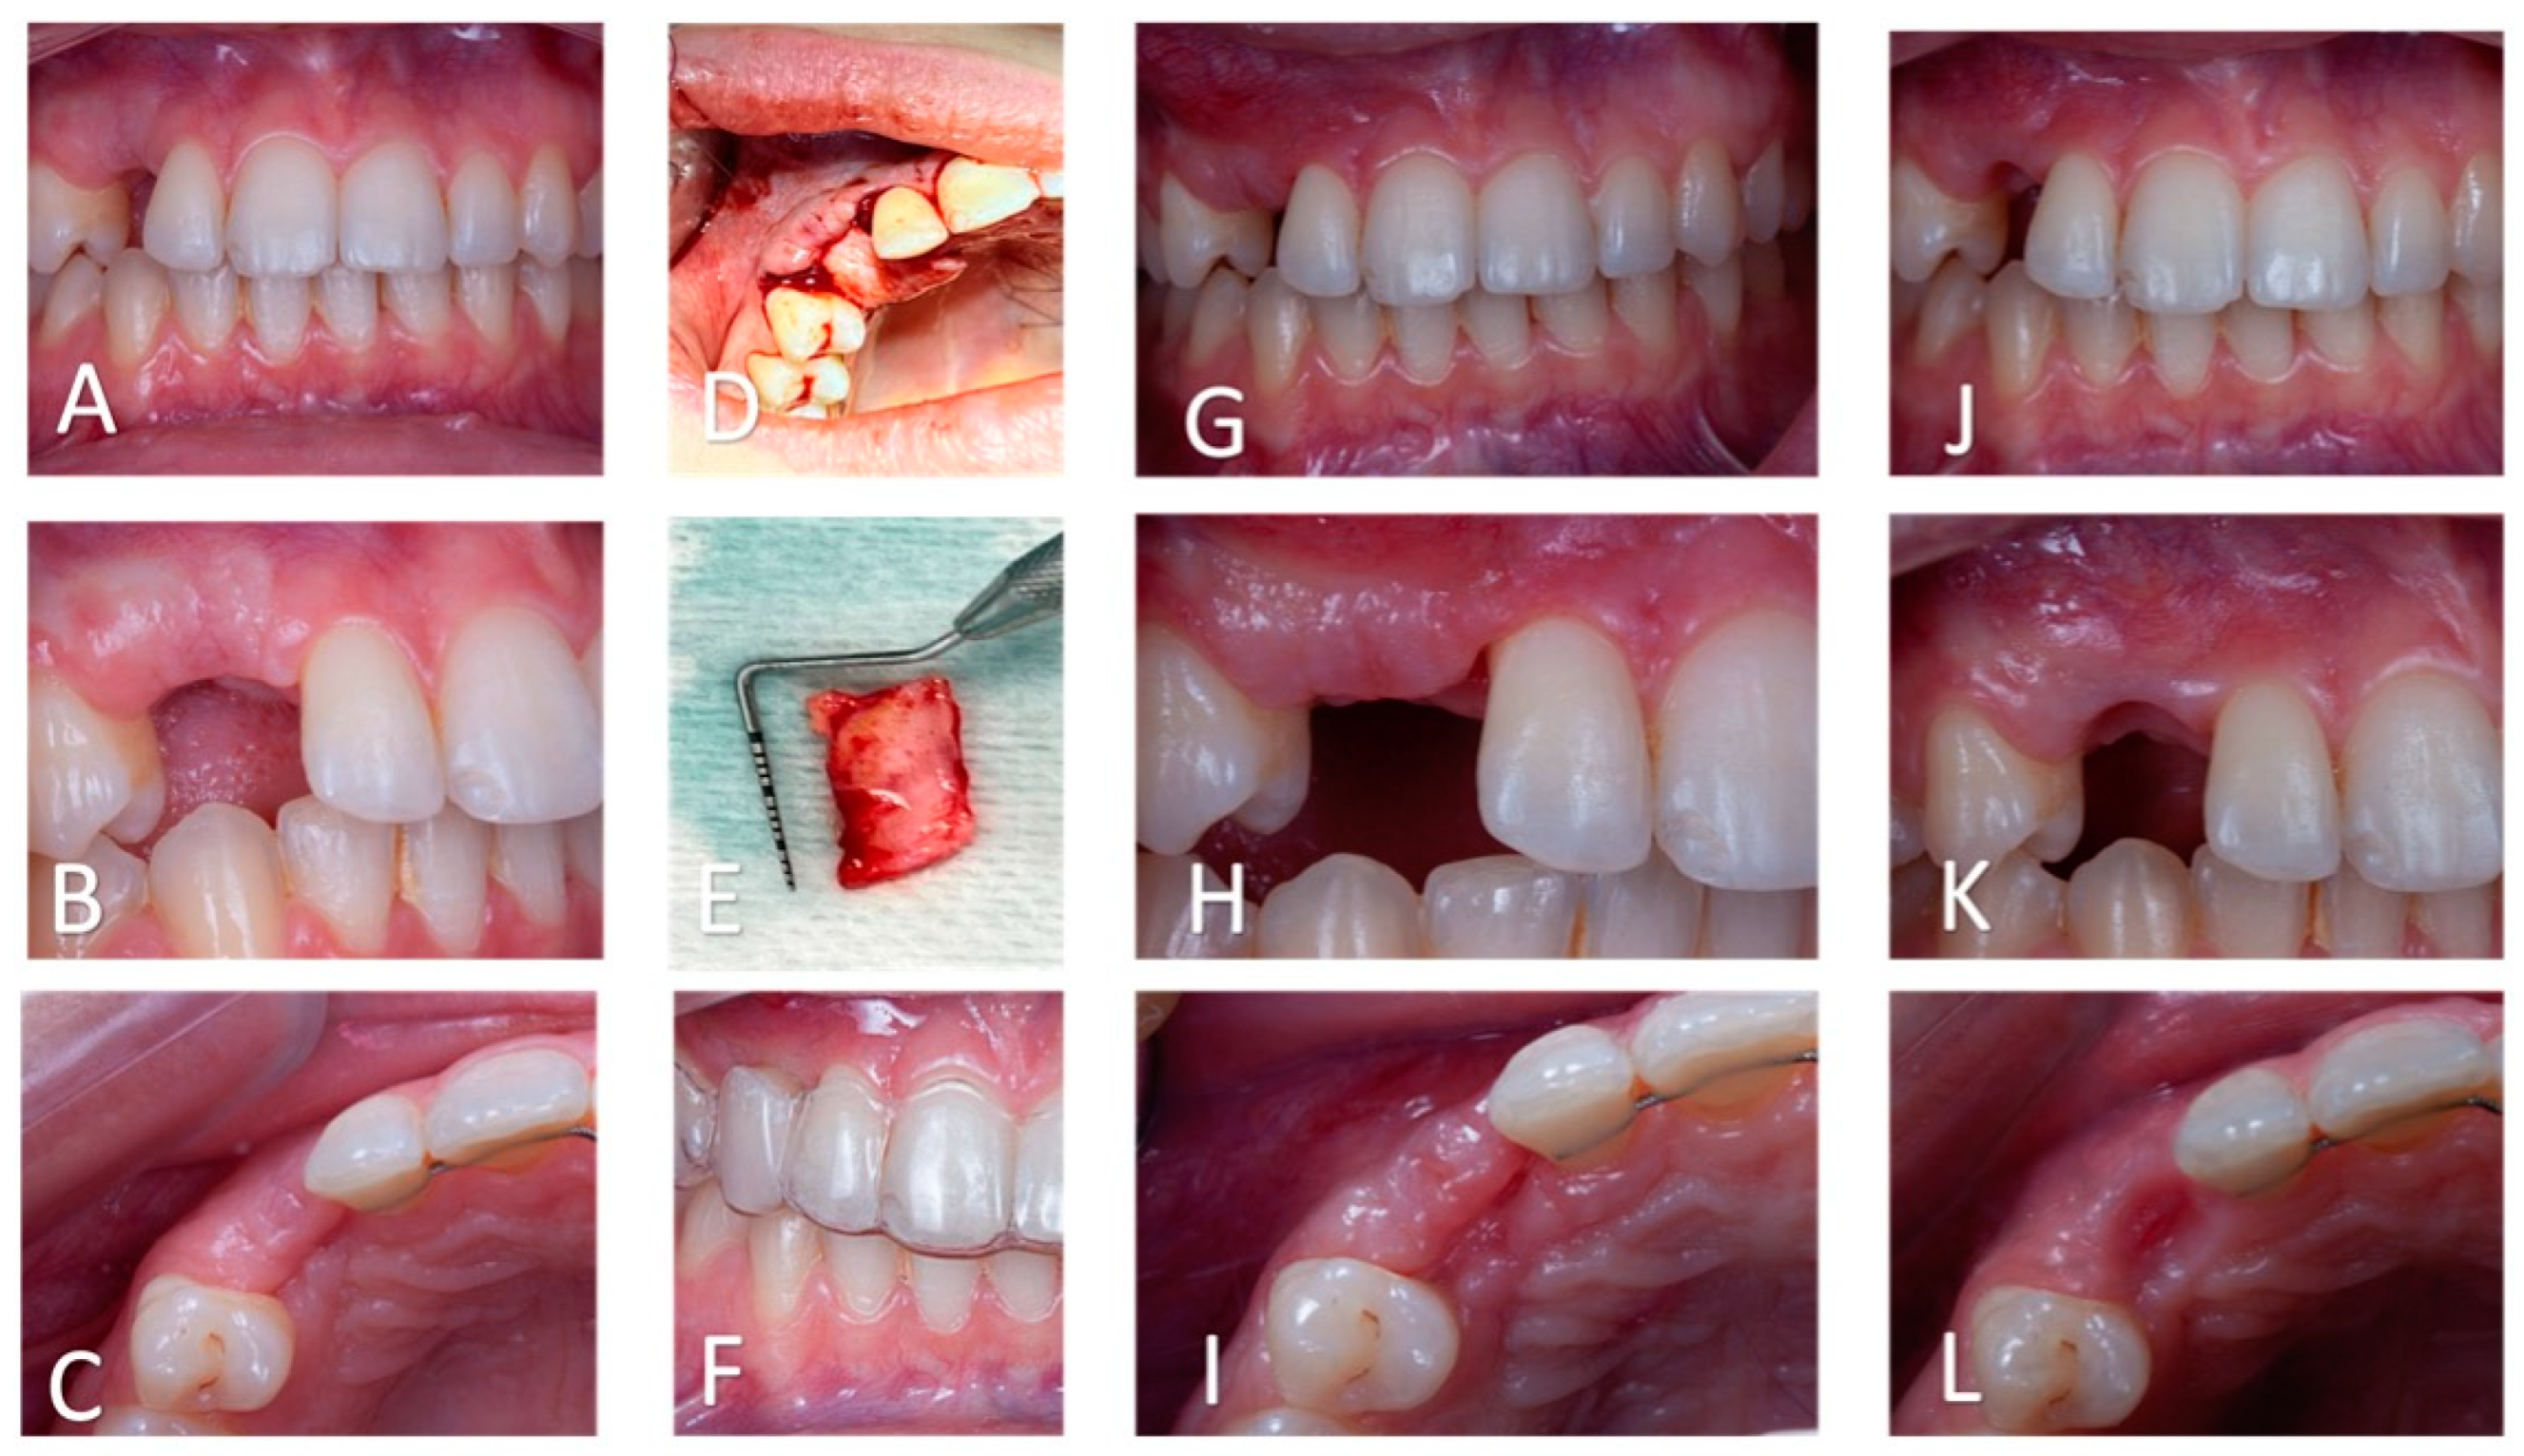

Figure 7. Soft tissue management. (AC): Intra-oral views (frontal, lateral, and occlusal, respectively) after decoronation and before periodontal surgery. The soft tissues are thin and the gingival lines of # 13 and # 23 are asymmetric. (D): Intra-oral pre-operative view of the mucogingival surgery. Buccal and supra-crestal placement of the graft. (E): Connective tissue graft. (F): Intra-oral frontal view with the vacuum-formed retainer, worn during healing. (GI): Intra-oral views (frontal, lateral, and occlusal, respectively) after periodontal surgery. An increase in the soft tissue thickness in the frontal and transversal planes is observed. (JL): Intra-oral views (frontal, lateral, and occlusal, respectively) after gingival modelling with the retainer and the veneer tooth. The gingival line is aesthetically pleasing.

Six weeks after the decoronation surgery, a connective tissue autograft was used to increase mucosal thickness at the edentulous site (Figure 7). The tissue was harvested from the palate in the premolar region opposite to the edentulous site. Gingival bed preparation was initiated following a 3-week healing period. A vacuum-formed retainer was used to shape the soft tissue. To create a natural gingival profile [8,9,10], flowable composite (Cirus Flow, Elsodent, Cergy Pontoise, France) was successively added to the apical part of tooth # 13 located inside the retainer (Figure 7).